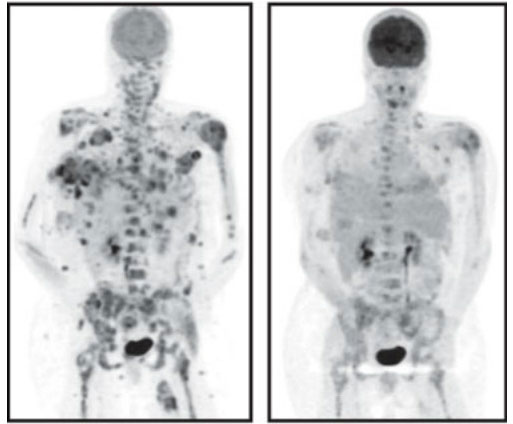

PET scan showing decrease in melanoma tumors using drug developed in part at SLAC Image courtesy Plexxikon Inc.

PET scan showing decrease in melanoma tumors using drug developed in part at SLAC.